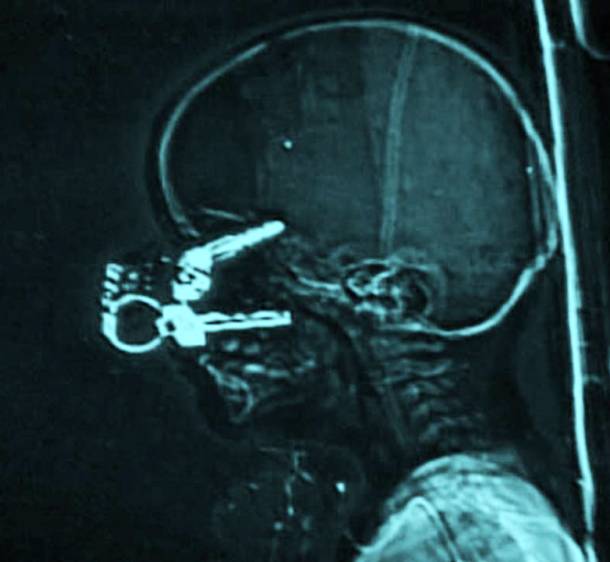

16. A Set Of Keys In A Child's Face

This little child was only 17-months old when somehow a set of keys ended up penetrating through his eye sockets and into his skull. Thankfully the baby managed to make a full recovery but the circumstances as to how and why this happened was also a matter that had to be investigated.Advertisement